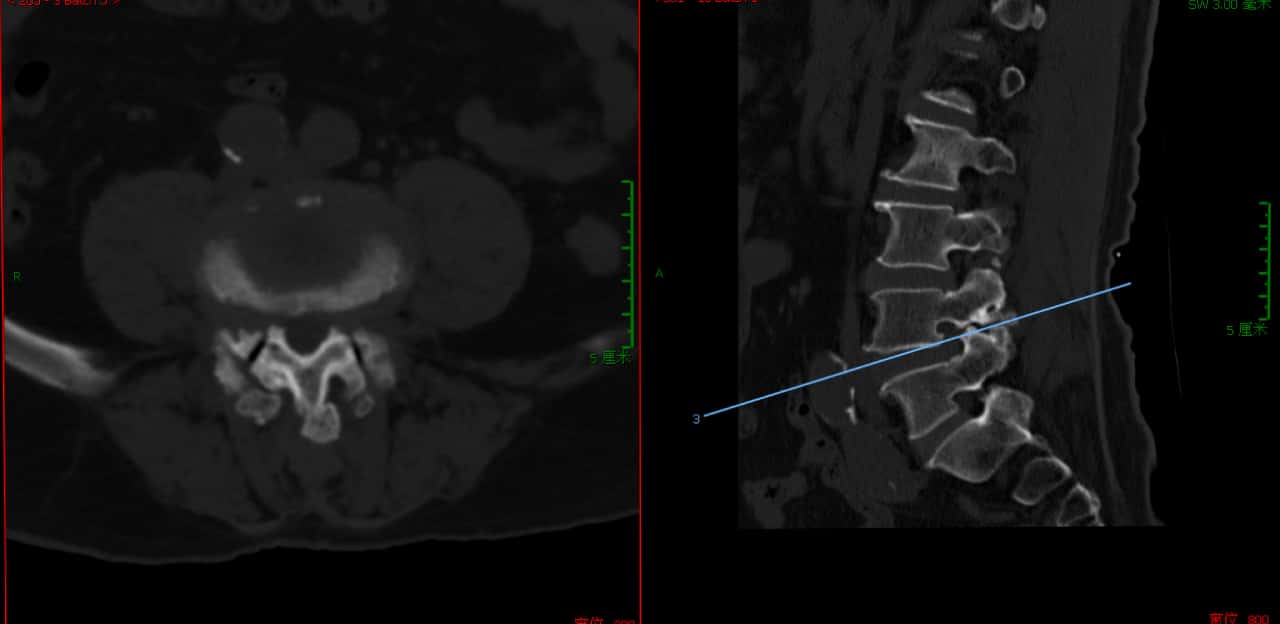

核磁上可见椎4/5间孔狭窄,神经根受压变形。

核磁上可见椎间孔狭窄,神经根受压变细。